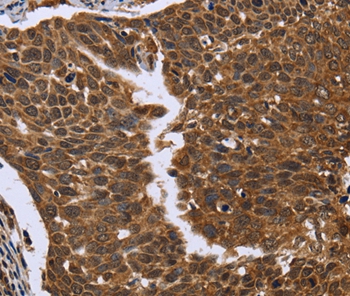

Immunohistochemical analysis of paraffin-embedded Human colon cancer tissue using #36479 at dilution 1/50.

Immunohistochemical analysis of paraffin-embedded Human cervical cancer tissue using #36479 at dilution 1/50.